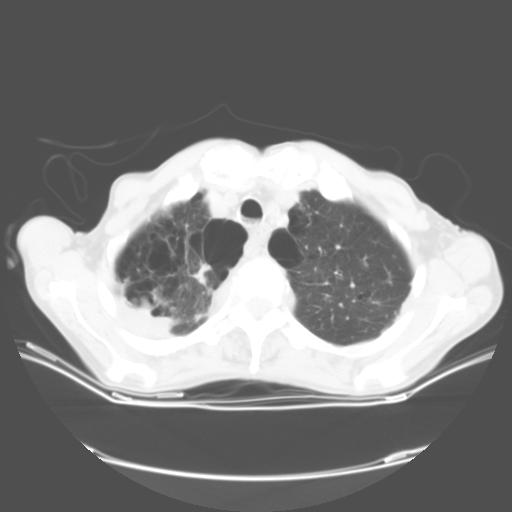

来院做头颅+胸部ct平扫

遂加作增强:

胸部病变平扫35hu,增强强化至70hu

这个病人首先是胸部病变的定位到底是肺内还是肺外。仔细观察块影位于胸膜下,与胸膜间有透亮带,且近端血管未见明显推移而是引流样改变,形态分叶,说明这个病灶位于肺内胸膜下。很可能是腺癌,腺癌最易致颅内高密度转移灶。局部胸膜有侵犯。

本例颅内见多发大小不等高密度灶,有强化及水肿;另外,胸锁关节层面可能是第四胸椎及右侧肋骨起始部骨质欠连续,椎旁软组织肿胀,建议调骨窗观察。

基于以上原因,所以炎性肿块或胸膜间皮瘤不考虑。

诊断:右下肺癌伴颅内、胸椎、肋骨转移可能性最大。

8楼版主所提的问题横好:此病例的讨论焦点应该是\"病灶的位置\".我认为其实质是“局限性胸膜间皮瘤与肺内肿块的鉴别诊断!”

我的诊断意见:肺内占位”病灶。片内骨质未见异常。

建议楼主提供强化的肺窗及双窗位图象{病灶边缘血管和支气管是否在病灶边缘突然中断换进入病灶内,如有可提示是肺内灶,如周围血管支气管有移位可提示是肺外病灶,如胸膜间皮瘤。胸膜间皮瘤的胸膜外脂肪层一般较清晰}。